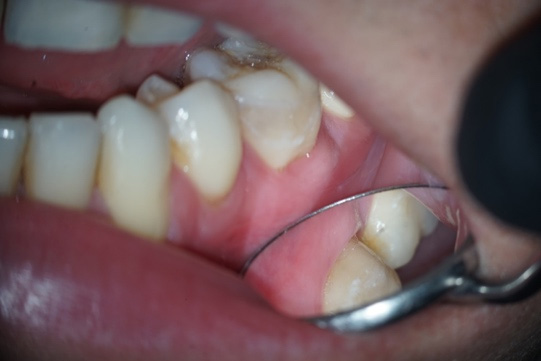

A 27-year-old male patient was referred for endodontic evaluation due to palpation discomfort in element 36. During anamnesis it was reported that the tooth had undergone endodontic treatment for two years and since then the tooth had edema by college entrance exam that disappeared and returned (Figure 1A). At radiographic examination, we observed that the previous treatment was unsatisfactory (Figure 1B), confirming the diagnosis of chronic apical abscess.

Figure 1: Clinical aspects (A)